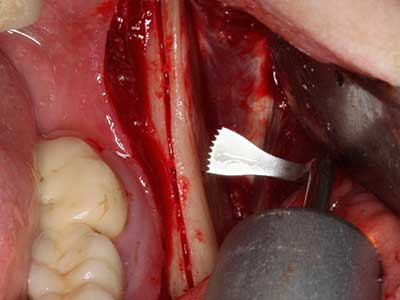

Quando le procedure chirurgiche vengono eseguite sull'osso nelle immediate vicinanze di strutture sensibili, come vasi sanguigni o nervi, gli strumenti rotanti pongono un rischio significativo di lesione iatrogena. I dispositivi piezoelettrici possono essere utili per la preparazione delle coperture ossee e la rimozione del tessuto duro in prossimità dei nervi, in particolare per la loro esposizione dopo una lesione iatrogena, ma anche durante la lateralizzazione dei nervi per le procedure di resezione e ricostruzione o il posizionamento di impianti (figg. 17-20). Il contatto leggero tra puntina piezoelettrica e nervo non causa generalmente danni, ma se si procede senza prestare attenzione con movimenti a sega o raccordi con residui di substrati ossei possono verificarsi danni al nervo temporanei o anche permanenti. Il rischio di danno, tuttavia, è considerato sostanzialmente inferiore al rischio presente utilizzando seghe o frese (Pereira, Gealh et al. 2014).